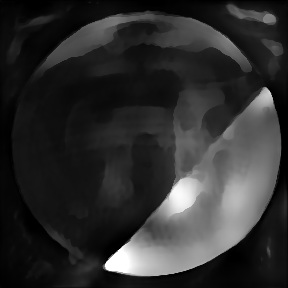

3.4 OCT

Optical coherence tomography (OCT) is a well established imaging technique based on low-coherence interferometry that enables volumetric imaging of biological tissue at high resolution (citep \@BBN(Pircher, 2018)). Light is split into a reference and a sample arm, recombined after being backreflected by a mirror and backscattered at different depths of the sample, in the respective paths. Using Fourier domain OCT (citep \@BBN(Fercher et al., 1995)), a tomographic image of the sample is reconstructed by spectral analysis of the resulting interference patterns. In order to achieve optimal axial resolution , it is essential to match dispersion between the two arms of the interferometer (citep \@BBN(Drexler et al., 2008)). This can be achieved on the one hand by carefully matching the length of the arms and the corresponding dispersive materials and on the other hand by numerical methods in the reconstruction process (citep \@BBN(Wojtkowski et al., 2004)). OCT was originally developed for imaging of the retina and, while there are many other applications of OCT available, its highest impact is to this day in ophthalmology, where this technology plays a critical role in correct diagnosis (citep \@BBN(Pircher, 2018)).

3.4.1 Reconstruction problem

Most commonly, OCT processing algorithms compute intensity images from the recorded spectral data. Standard algorithms include a step that performs numerical dispersion compensation. Methods are available which automatically determine the correct dispersion compensation parameter (citep \@BBN(Wojtkowski et al., 2004)), but the stability of automatic numerical dispersion compensation methods under varying imaging conditions is not yet fully understood. Besides the dispersion parameter, there exist also algorithms that provide geometrical corrections within the reconstruction process, see e.g. (citep \@BBN(Shirazi et al., 2020)), namely the correction of rotation introduced by eye motion and correction of the curvature of the retina. Automatic parameter selection for the geometric corrections is a challenging task which has so far not been addressed and therefore these parameters are usually set manually, which is very time-consuming especially in the case of clinical studies where often a large number of patients and imaging locations is included.

3.4.2 Data

We employ image data obtained using an adaptive optics (AO) supported spectral domain OCT system (citep \@BBN(Brunner et al., 2021)), where cross-sectional images (B-scans) were retrieved from two AO-OCT volumes recorded in a young healthy volunteer with a field of view of approximately 4×4superscript4superscript44^{\circ}\times 4^{\circ}4 start_POSTSUPERSCRIPT ∘ end_POSTSUPERSCRIPT × 4 start_POSTSUPERSCRIPT ∘ end_POSTSUPERSCRIPT (corresponding to  1.4×1.4mm1.41.4𝑚𝑚1.4\times 1.4mm1.4 × 1.4 italic_m italic_m on the retina). Different imaging locations and focus settings were considered. One data set was recorded in the fovea with the focus of the imaging beam set to the posterior retina and one data set close to the optic disc with the focus shifted to the anterior retina. An algorithm including dispersion compensation and geometrical corrections was employed (citep \@BBN(Shirazi et al., 2020)) for the reconstruction. The reference images, (a) in Figure 9 and 10, were obtained by manually optimizing over the parameters that define the compensation of dispersion, rotation and curvature, respectively. The examples in Figure 9 and 10 compare the chosen reference to three sub-optimal reconstructions, where (b) had a bad choice for the rotation correction parameter, (c) for the curvature correction parameter and (d) for the dispersion compensation parameter.

Refer to caption

(a) Reference

(b) (26.88, 0.71, 0.05)

(c) (26.84, 0.72, 0.04)

(d) (29.94, 0.77, 0.06)

Figure 9: OCT reference reconstruction (a) and reconstructions with sub-optimal parameters (b)-(d) leading to geometric deviations (b)-(c) and low resolution (d). Here, (d) is wrongly judged as best reconstruction by SSIM and PSNR, LPIPS is able to ignore the small spatial deviations.

(b) (25.20, 0.55, 0.04)

(c) (26.49, 0.66, 0.03)

(d) (27.78, 0.70, 0.06)

Figure 10: OCT reference reconstruction (a) and reconstructions with sub-optimal parameters (b)-(d) leading to geometric deviations (b)-(c) and low resolution (d). Here, (d) is wrongly judged as best reconstruction by PSNR and SSIM, LPIPS is able to ignore the small spatial deviations.

FR-IQA mismatches

Good dispersion compensation should provide images with a depth resolution that is optimized for the system at hand. In the ophthalmic application of AO-OCT, this high axial resolution allows for the visualization and identification of the different retinal layers (citep \@BBN(Shirazi et al., 2020; Brunner et al., 2021; Wojtkowski et al., 2004)), different retinal layers and structures, such as blood vessels. In the first example Figure 9 the clear separation of the different layers in the posterior retina, such as the photoreceptor bands and the retinal pigment epithelium, is crucial for clinicians/researchers who investigate the structure and function of the healthy and the diseased human retina (citep \@BBN(Jonnal et al., 2014)). Therefore, in this example, the reconstruction shown in Figure 2 (d) should have been rated the lowest as the axial resolution is the lowest because of faulty dispersion compensation, which cannot be fixed by further post-processing. In the second example Figure 10, a cross-sectional view of three retinal vessels which are embedded in the nerve fibre layer is given. Changes in the thickness of vessel walls are an important early biomarker for retinal diseases such as diabetic retinopathy, cf. (citep \@BBN(Bakker et al., 2022)). Again, the reconstruction with faulty dispersion compensation shown in Figure 10(d) should have been rated the lowest. The loss in axial resolution worsens the visualization of the vessel walls and would lead to inaccurate measurements of the vessel wall thickness.

In the current version of the algorithm the parameters which determine the amount of dispersion, rotation and curvature compensation applied by the reconstruction algorithm have to be set manually. Therefore, automated evaluation would be very helpful to fasten the process. PSNR and SSIM are not suitable to assess the problem correctly, as they penalize the spatial deviations in (b) and (c) strongly. The geometric deviations are not beneficial, but these errors could be corrected in an additional post-processing step unlike the deteriorated axial resolution due to the wrong dispersion compensation parameter (d). LPIPS is able to ignore this small spatial deviations.